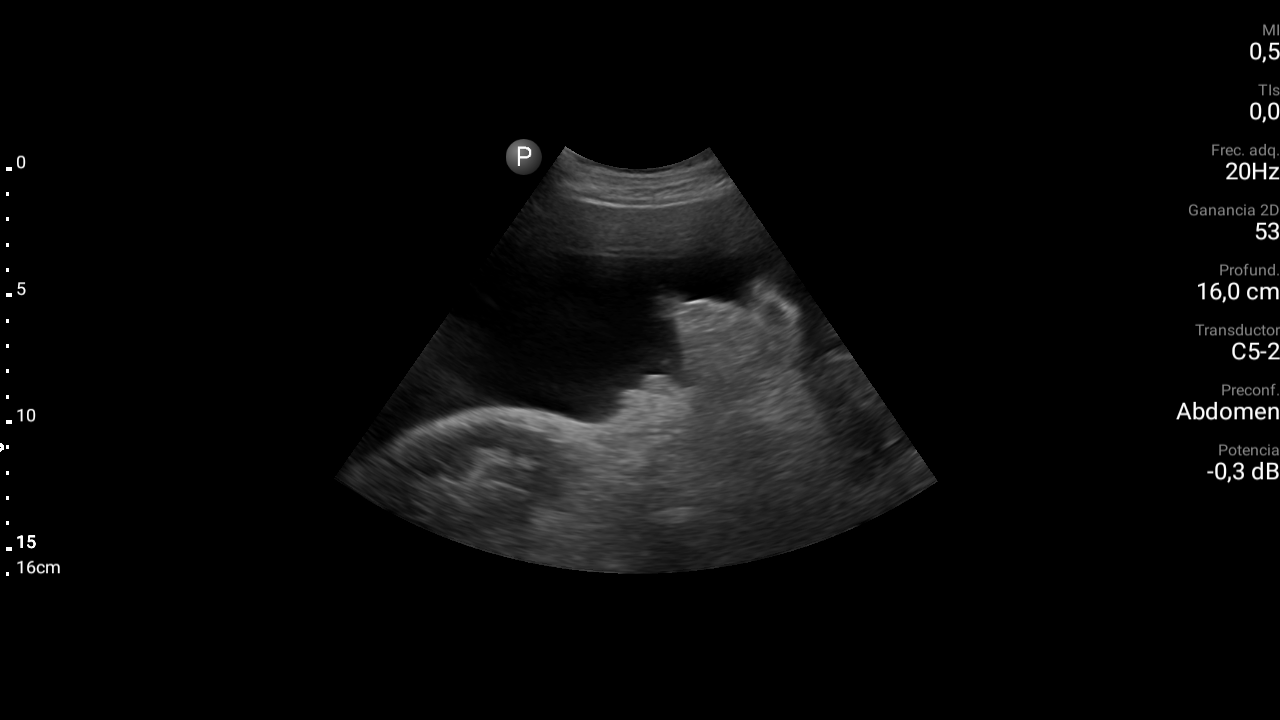

Presencia de ascitis perihepática, periesplénica. En la pelvis se visualizan asas intestinales con aspecto congestivo.

Derrame pleural bilateral moderado.

TC abdominal: Estigmas de hepatopatía severa (hígado de bordes nodulares e hipertrofia del lóbulo caudado) Ascitis peritoneal. Aspecto congestivo asas de delgado. Estigmas de hipertensión portal con circulación colateral destacando presencia de varices rectales. Derrame pleural bilateral